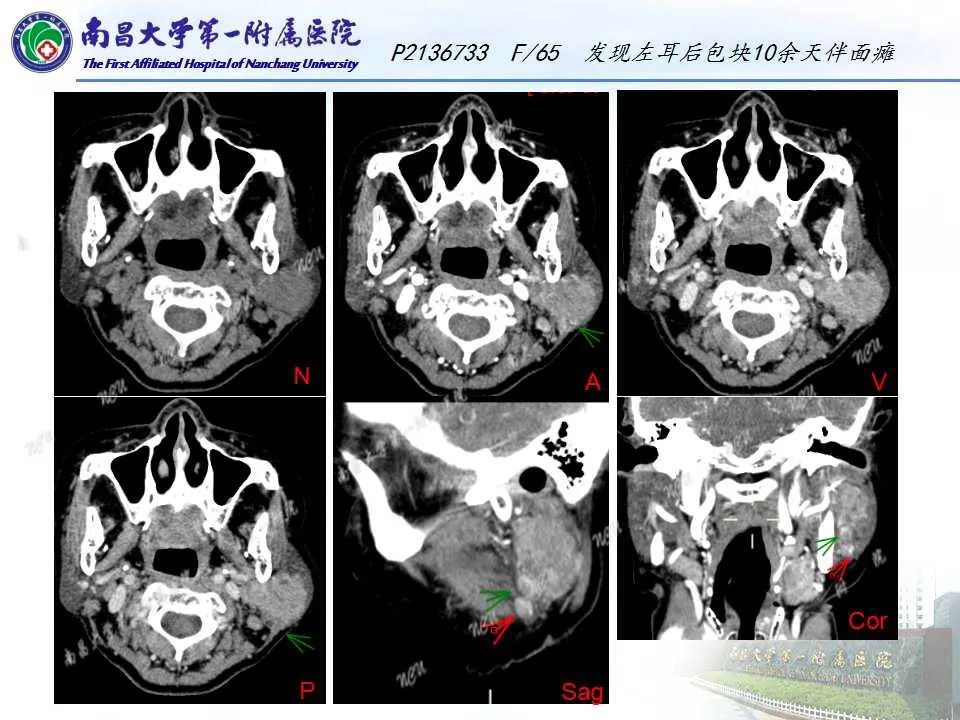

【PPT】腮腺肿瘤CT诊断分析思路